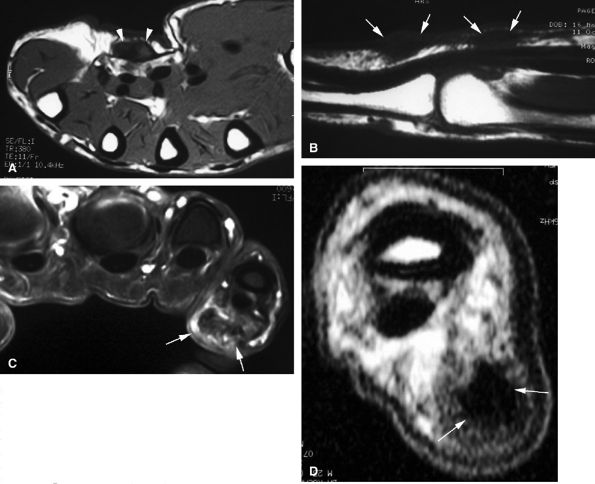

FIGURE 11.31 ● Mallet finger. (A) Fracture avulsion (arrow) of the base of the distal phalanx (lateral view). (B) Sagittal T1-weighted images in a different case showing a tear of the terminal band of the extensor apparatus (arrows) with thickening of soft tissues. There is bone edema (arrowhead) of the base of the distal phalanx without fracture.

|